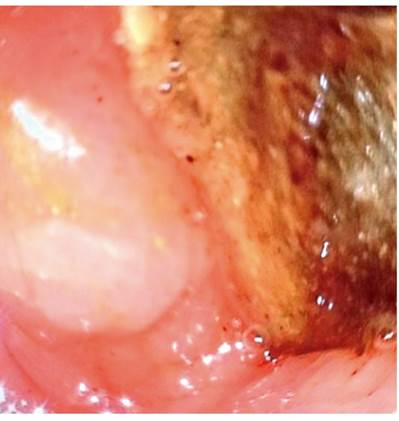

The abdominal CT scan showed intestinal obstruction as an intraluminal image in the first 4.5 x 3 cm duodenal portion (Figure 1 and 2). It was associated with pneumobilia and contrasted bile duct passage. This meets the criteria of Rigler’s triad. In addition, upper digestive tract endoscopy showed dilatation of the gastric chamber secondary to obstruction of the duodenal lumen and an impacted calculus in the duodenal bulb (Figure 3 and 4).

Given the clinical findings, paraclinical findings, and images, Bouveret syndrome was diagnosed, and we performed an exploratory laparotomy with gastrostomy and extraction of the stone impacted in the duodenal bulb followed by gastrorraphy (Figure 5 and 6). During the surgery, inflammation became evident with multiple adhesions on intestinal loops from the omentum to the liver and gallbladder. This made visualization difficult.

Figure 5 Removal of stone lodged in duodenal lumen through open gastrostomy. The image shows the anterior wall of the open gastric corpus from which the calculus was extracted.